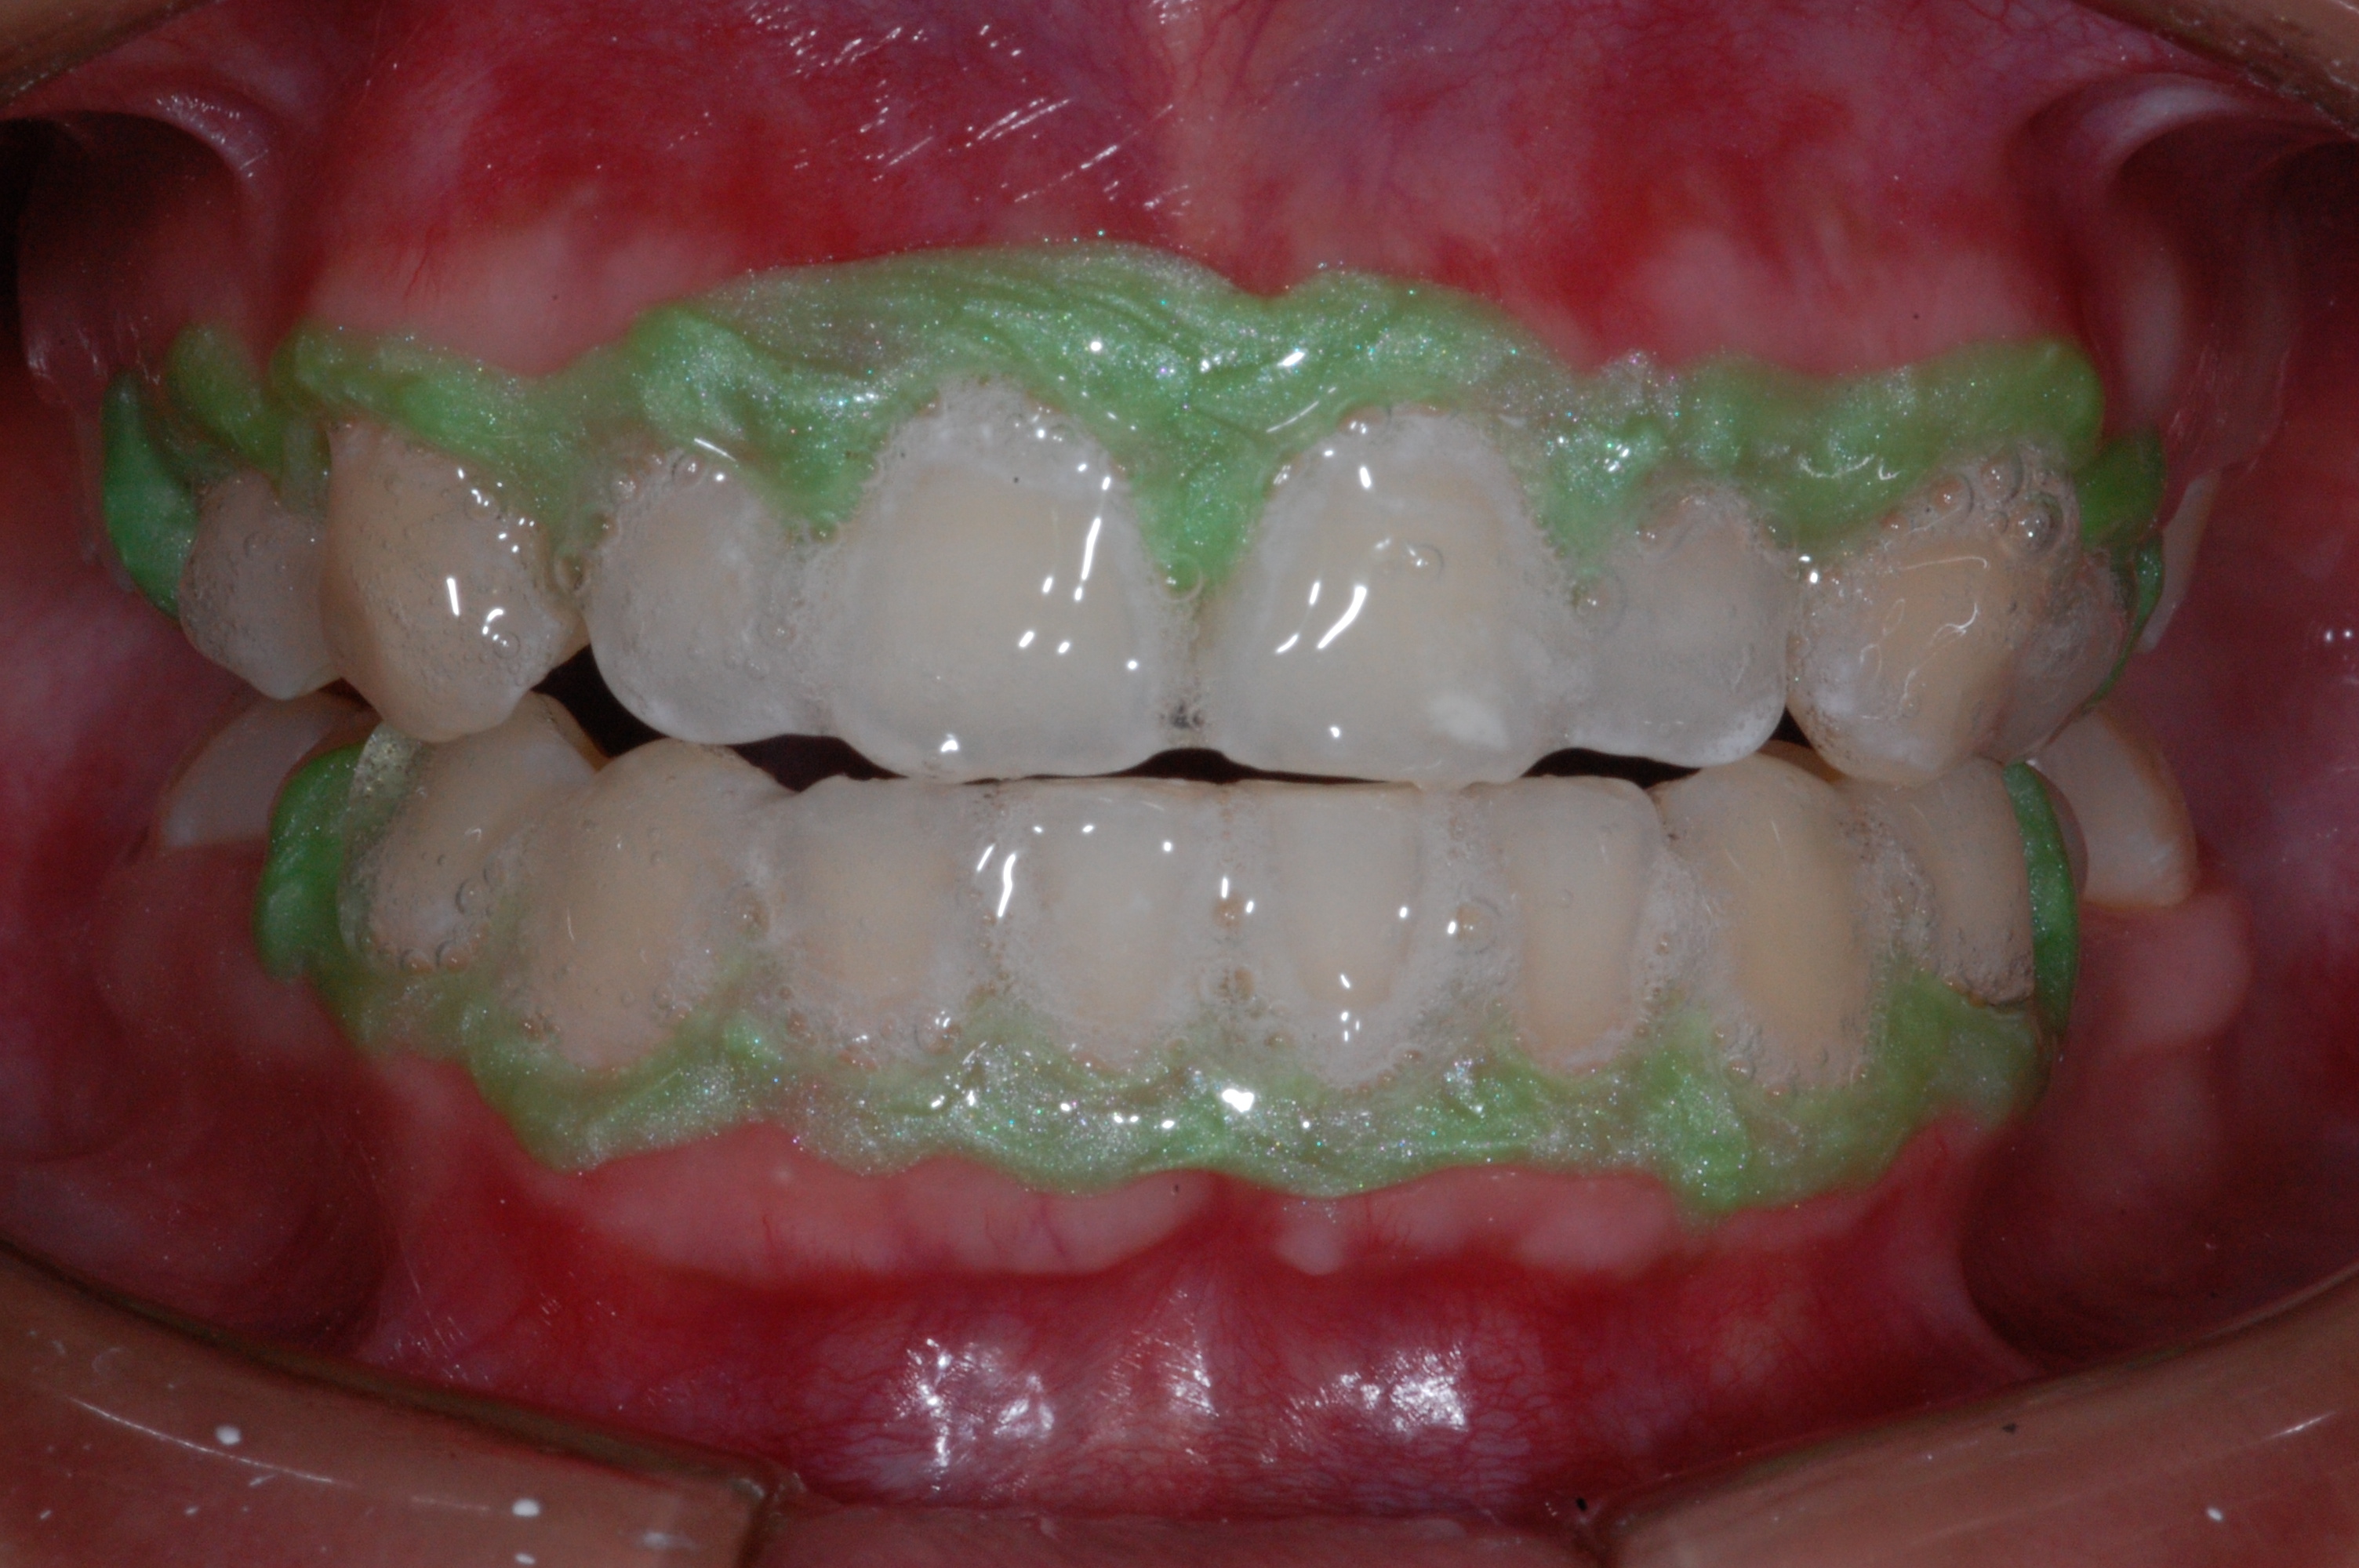

The presence of diastema, between anterior teeth, distorts a pleasing smile by concentrating the observer’s attention on the spaces. The patient’s needs and expectations must be considered in the process of treatment planning to ensure satisfaction with the treatment outcomes. There are many forms of therapy that can be used for diastema closure. A carefully developed diagnosis, which includes a determination of the causal elements and advanced treatment planning, allows the most appropriate treatment to be selected for each case. The aim of this paper is present a multidisciplinary approach as a solution to multiple diastemas in the anterior region using gingival tissue recontouring and direct adhesive restorations, with minimum wear of the dental structure, after the orthodontic intervention discussing the minimal intervention to obtain imperceptive and aesthetic final restoration. Thirty-six months after the treatment was carried out, the final aesthetic was maintained with all dental element details and gingival tissue harmony, without recurrence of periodontal pockets and the preservation of the tooth color and shape.